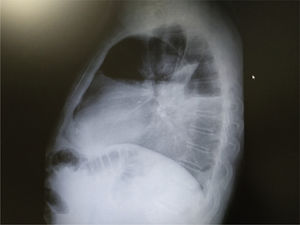

Radiografía de tórax de perfil (fig. 2): ángulo costofrénico borrado.